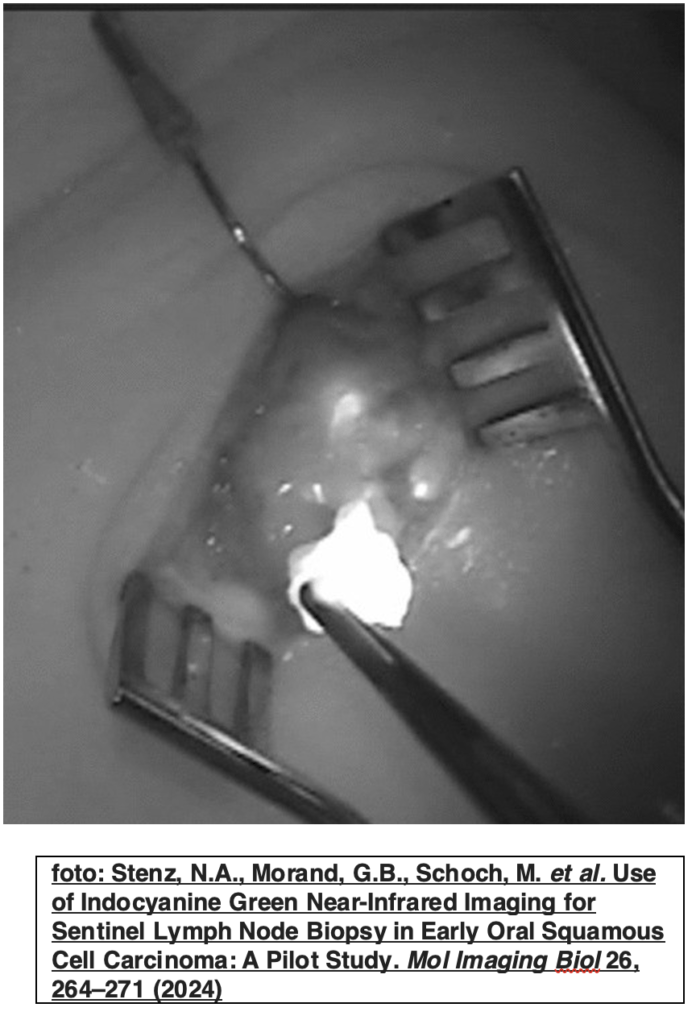

Uno studio multicentrico statunitense illustra i vantaggi dell’utilizzazione combinata delle immagini near infrared (NIR) dopo somministrazione della colorazione indocianina green associata all’utilizzo intraoperatorio del gamma probe nella identificazione del Linfonodo sentinella (SN) nei Tumori Cervico Facciali.

I pazienti indagati sono stati 21. In tutti i casi l’associazione delle due metodiche ha agevolato il chirurgo nella identificazione del SB, aggiungendo la visualizzazione cromografica alla radiocaptazione.